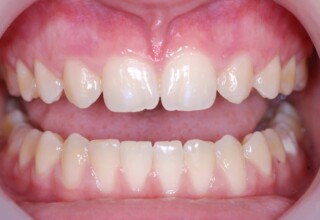

Αποκατάσταση διαστημάτων μεταξύ κεντρικών και πλαγίων τομέων

Τα διαστήματα έχουν δημιουργηθεί κυρίως λόγω των στενών πλαγίων. Μετά την ολοκλήρωση της ορθοδοντικής θεραπείας τα διαστήματα “έκλεισαν” με την τοποθέτηση δύο αποκαταστάσεων σύνθετης ρητίνης.